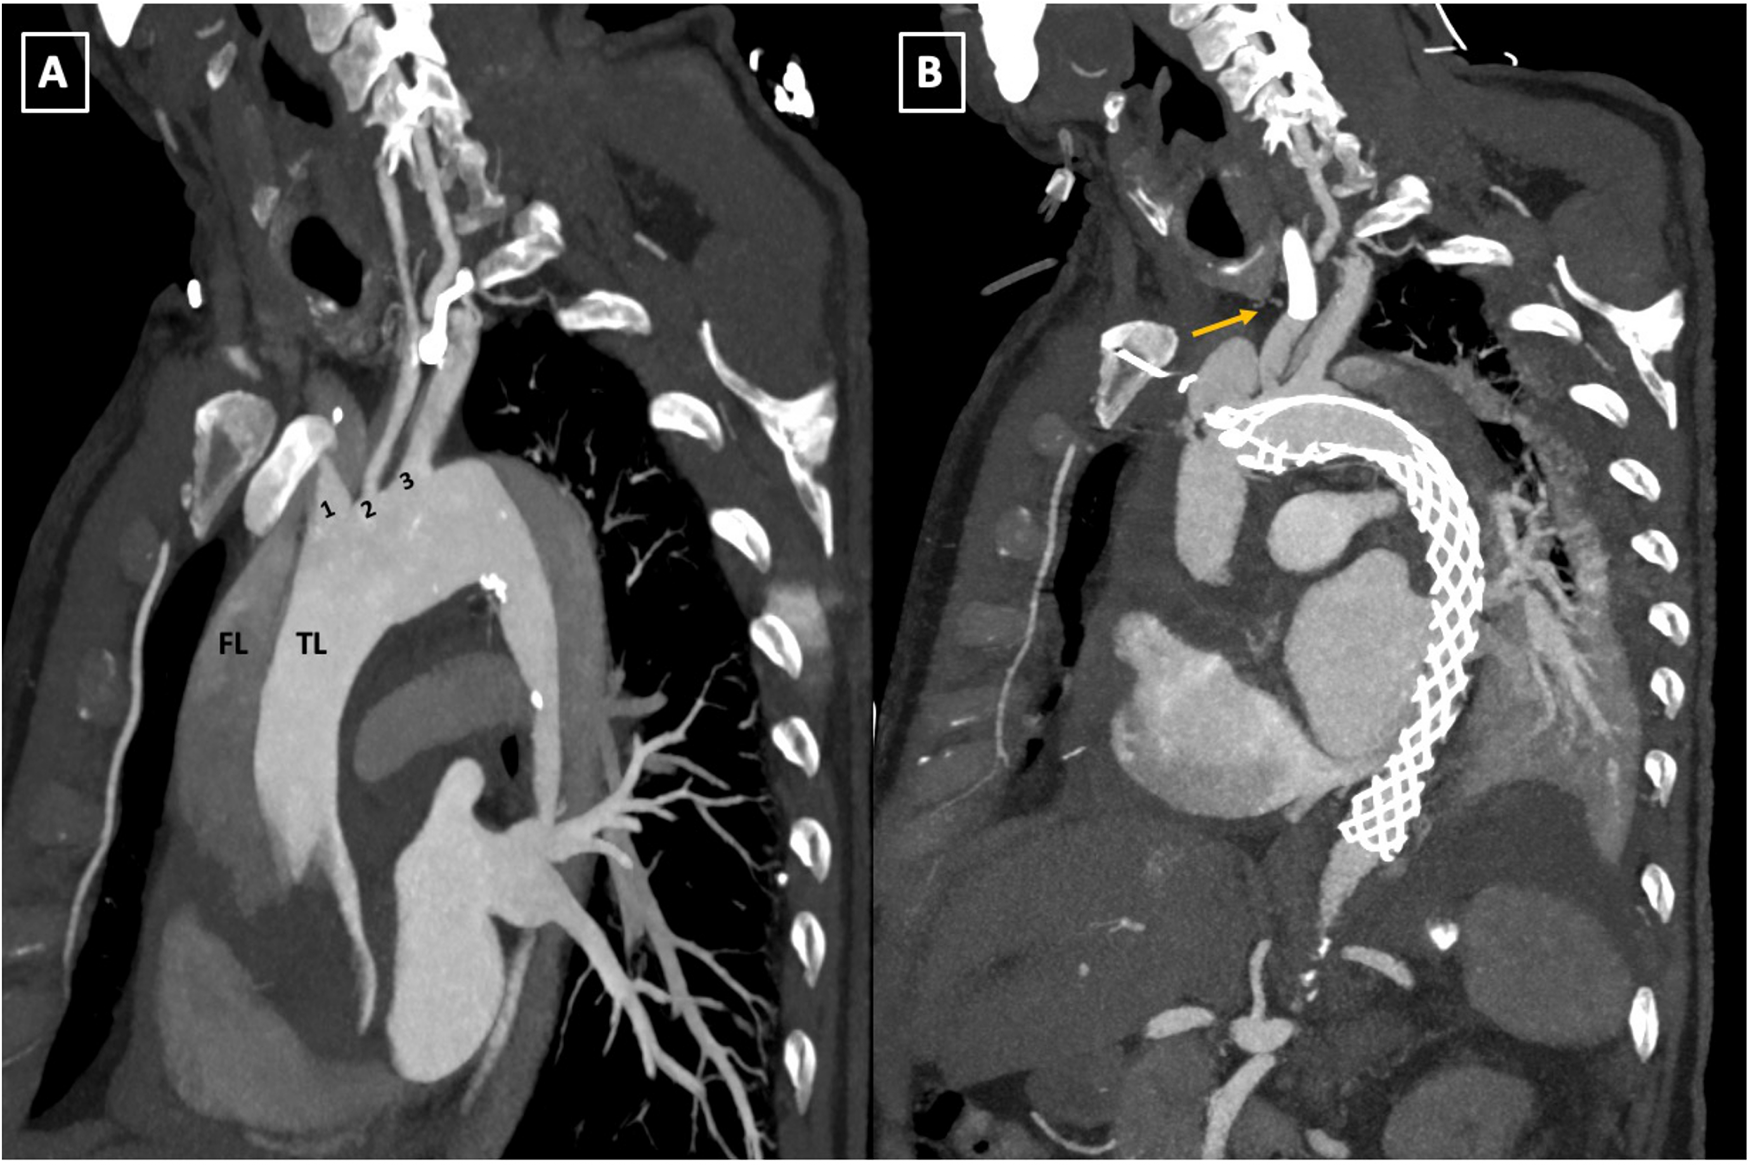

Postoperatively, the patient displayed right anisocoria and aphasia, with cerebral CT identifying bilateral occlusion of internal carotid arteries with a patent basilar artery (Figures 4A,B). Furthermore, the Maximal Intensity Projection (MIP) reconstruction highlights the distal filling of the right internal carotid artery through the patent right posterior communicating artery (Pcom). Notably, the left Pcom is absent, resulting in insufficient collateral flow to the left cerebral hemisphere. The Angiography revealed significant restriction of antegrade flow in the LCCA, markedly diminishing ipsilateral intracranial circulation. Endovascular stenting via the AMDS successfully recanalized the artery. Subsequent angiography post-stent deployment showcased restored patency in the LCCA and markedly improved circulation within the left carotid territory (Figures 4C, 5A,B).

Figure 5

(A,B) Pre-and postoperative follow-up computed tomography angiography (CTA) scan comparison. The parasagittal reconstruction view of the aortic arch demonstrates changes placement of the AMDS stent in zone 0 of the aortic arch and left common carotid artery (LCCA) endovascular stent deployment (arrow, B). TL, true lumen; FL, false lumen; 1, innominate artery; 2, left common carotid artery; 3, left subclavian artery; AMDS, ascyrus medical dissection stent.